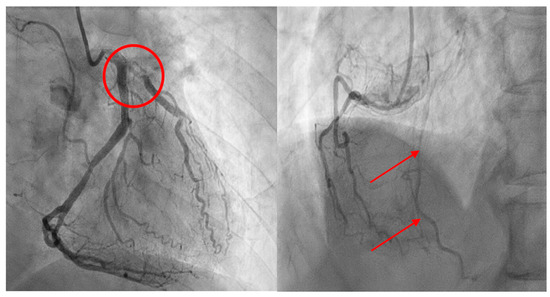

2. Case Presentation